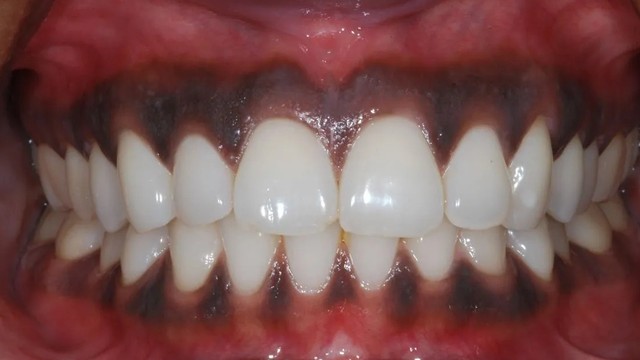

/https://cms-prod.s3-sgn09.fptcloud.com/nuou_rang_bi_den_86c6195639.jpg)

Khi nướu răng khỏe mạnh sẽ có màu hồng san hô tự nhiên. Sự thay đổi màu sắc của nướu răng có thể là một dấu hiệu cảnh báo vấn đề về sức khỏe răng miệng. Một số người gặp tình trạng nướu răng bị đen. Để biết thêm nguyên nhân, triệu chứng và cách điều trị nướu đen, bạn đừng bỏ qua bài viết này nhé!